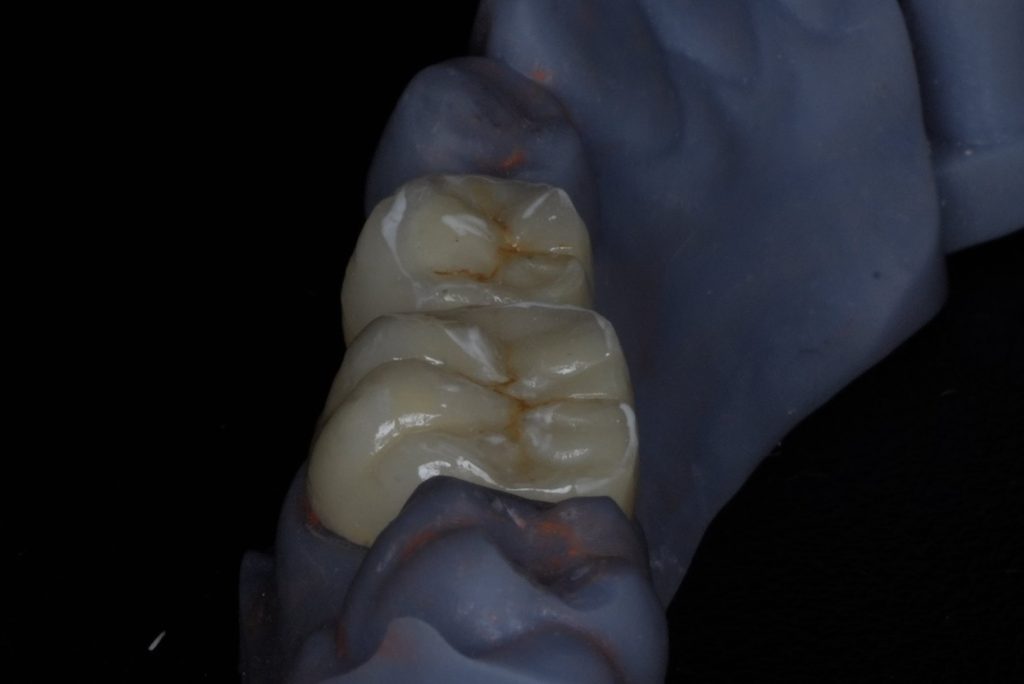

A dual-cure resin core (Clearfil DC Core Plus) was bonded using 4th-generation adhesive (Clearfil SE Bond 2). Tooth preparation followed the principles of adhesive ferrule preservation with rounded internal line angles (Fig 2).

- Fig 2: Post-endodontic core build-up and crown preparation.